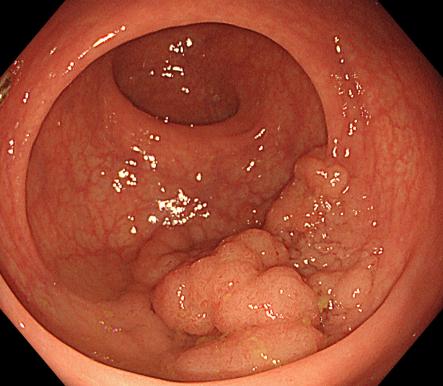

3b2d4fd666c540e5a8957f178dfb0b6b.Jpeg38cdda0ed1d245cfa077b1a308a229ca.Jpeg

內痔                    內鏡下內痔硬化治療

內鏡下內痔硬化術:治療I-Ⅲ度內痔伴有內痔相關癥狀;I~Ⅲ級內痔飲食及藥物治療無效;內痔手術后復發,肛門反復手術后不能再次手術;恐懼外科手術,不愿意接受手術治療;高齡、高血壓、糖尿病和嚴重的系統性疾病,不能耐受外科手術等。